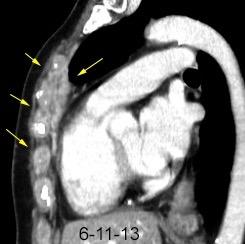

102. HEMATOMA MEDIASTÍNICO.

Hematoma retroesternal y pericárdico en cirugía de válvula mitral. Migración de suturas